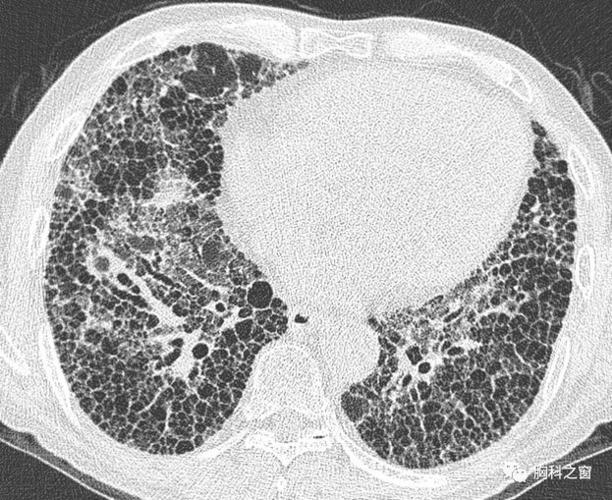

肺间质纤维化晚期——两肺蜂窝影

实变四,牵拉性支扩三,磨玻璃密度二,网状影和线状影一,蜂窝肺间质病变